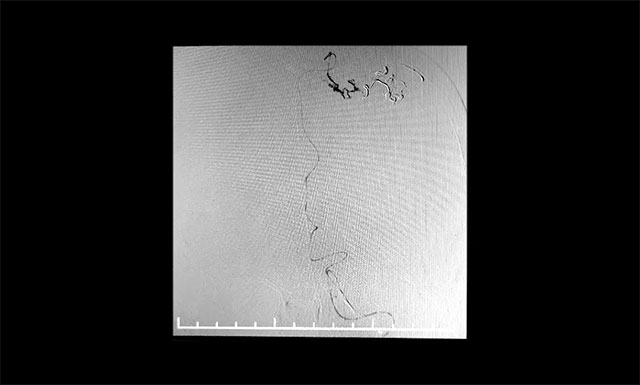

▲ DSA检查显示,中央后回动静脉畸形

患者为55岁男性,4月份突发右眼失明,头颅CT+CTA显示,左侧顶叶异常强化灶,考虑血管畸形AVM可能。经医院DSA检查,确诊为功能区动静脉畸形,畸形团分布较弥散,位于中央后回,主要由大脑前动脉分支供血,通过皮层静脉向上矢状窦引流。该患者畸形血管团体积较大,且与其相连的供血动脉及回流静脉交织纷乱、复杂、异常粗大,病灶紧邻运动中枢、语言中枢、书写中枢等重要结构。